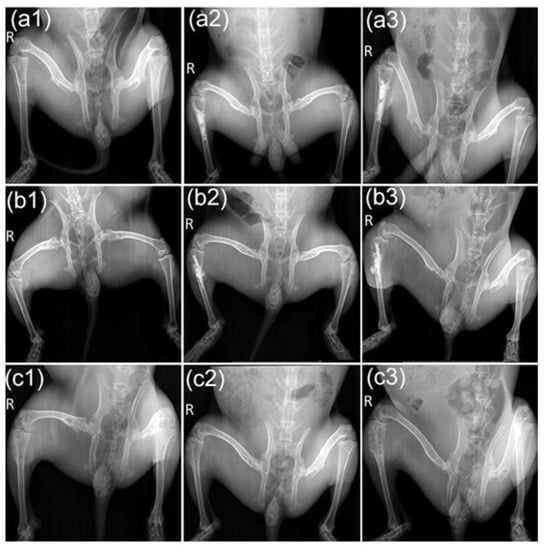

We further evaluated bone resorption using X-ray and micro-CT scans. The X-ray image was first roughly examined using the morphologic changes of the tumor-bearing tibias. As shown in Figure 5, with the pre-injection of M-PMMA, the cortical bone thicknesses and trabecular separation of the tumor-bearing proximal tibias were similar to the healthy hind legs in the three groups (Figure 5a1,b1,c1). Post-injection of M-PMMA, high-density bone cement was located in the cavum medullare of the tumor-bearing proximal tibias (Figure 5a2,b2). The volume of M-PMMA was calculated before injection (0.7–1.0 mL). At the end of the magnetic treatment, the tumor-bearing proximal tibias of rabbits in the M-PMMA and control groups were severely destroyed, and the surrounding soft tissues were swollen (Figure 5c1,c2), while those in the M-PMMA + AMF group were less damaged (Figure 5c3). Although thinning of the cortical bone was observed, the tibial shape was well maintained in the M-PMMA + AMF group.

Figure 5. X-ray images of the animal models. Images of hind legs in the M-PMMA + AMF group pre-injection (a1), after (a2) magnetic bone cement injection, and at the end of magnetic hyperthermia (a3). Images of the M-PMMA group (b1b3) and the control group (c1c3) at the same time point.